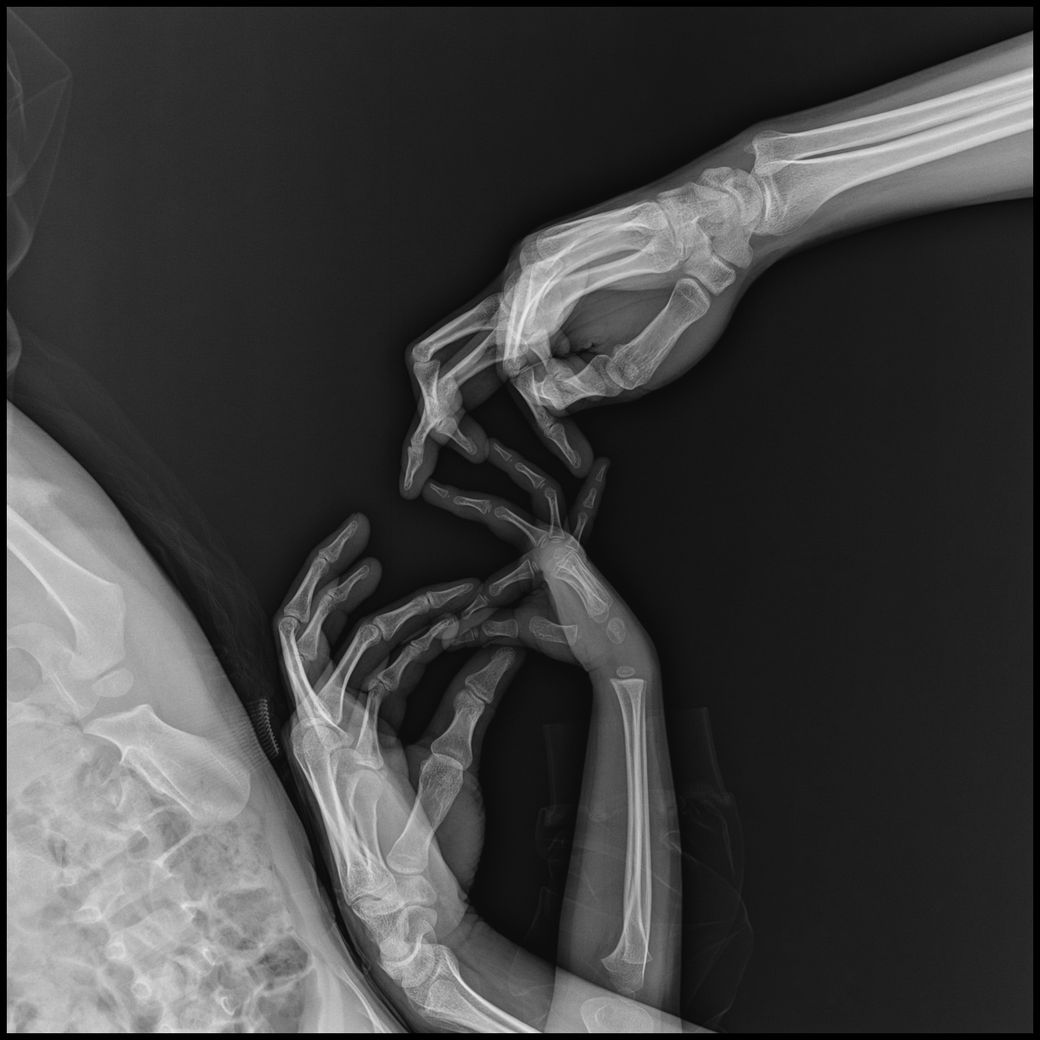

• 2번 째 사진

- 손부터 팔꿈치까지 : 3장